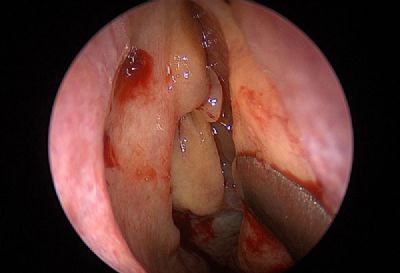

הטיפול בסינוסיטיס מתרכז במתן אנטיביוטיקה לצורך דיכוי הזיהום והקלה על תסמיני המחלה. כפי שכבר ציינו, חלק מחולי הסינוסיטיס סובלים אף מנזלת כרונית. זוהי הסיבה לכך שישנם רופאים המשלבים מתן סטרואידים לאף לטיפול מקומי בצורת תרסיס עם הטיפול הניתן לסינוסיטיס כרוני. בחלק מהמקרים ישנו צורך בהתערבות כירורגית על מנת לנקות את גתות האף מרקמה מוגלתית פגועה.

סינוסיטיס כרוני היא מחלה אלרגית

בעבר מקובל היה לחשוב שהסיבה לסינוסיטיס כרוני היא זיהום חיידקי בגתות האף ולהציע לחולים טיפול אנטיביוטי. אך המחקרים האחרונים שוללים את המקור הזיהומי של מחלה זו. למעשה, הטיפול האנטיביוטי אינו יעיל בחולים הסובלים מסינוסיטיס כרוני. הגורם האמיתי למחלה הן פטריות עובש – אלרגנים נפוצים. מחקרים מדעיים מראים שלכמות חלקיקי פטריות אלה הנמצאים באוויר ובחלל האף קשר ישיר לחומרת הדלקת ברירית גתות האף. יתר על כן, הרחקת חלקיקים אלה מהסביבה ומחלל האף גורמת להקלה משמעותית במהלך הסינוסיטיס הכרוני. נציין גם שדלקת אלרגית כרונית, שמקורה בפטריות עובש, גורמת להגדלת פוליפים באף ולעיבוי הרירית, מה שמקשה עוד יותר על הפרשת הליחה. פוליפים קיימים גורמים לזיהומים משניים ומזרזים את תהליך ההגדלה של פוליפים נוספים. כך נוצר מעגל קסמים הגורם לדלקת כרונית בגתות האף.

הטיפול בסינוסיטיס כרוני: שלב ראשון – פיקוח על אוכלוסיית פטריות עובש!

החלק החשוב ביותר בטיפול הוא מציאת אוכלוסיית פטריות עובש בבית (לרוב הן שוכנות במקומות עם לחות גבוהה) וכן וויסות אחוזי הלחות בתוך הבית. מומלץ אף לקחת דגימות אוויר על מנת לחשב את רמות הזיהום על ידי נבגי עובש בתוך מבני מגורים. לרוב עוסקות בכך מעבדות מיוחדות. באפשרותך להזמין בדיקה זו באמצעות המרפאה שלנו. במהלך הבדיקה ממוקמת צלוחית מיוחדת המכילה סביבה מזינה עבור פטריות העובש למשך שעה במקומות המועדים לפורענות (חדר שינה, מטבח, סלון ומקלחת). לאחר מכן שולחים את הצלוחיות למעבדה לביצוע בדיקה. אם בעת הספירה נמצאות מעל לארבע מושבות של פטריות עובש, ישנו צורך לבצע טיפול מיוחד נוגד עובש בבית. סביר להניח ששמירה על אוויר נקי בהמשך (צמיחה של < 4 מושבות של פטריות עובש בבדיקת מעבדה) תביא להקלה משמעותית במהלך סינוסיטיס ונזלת כרוניים.